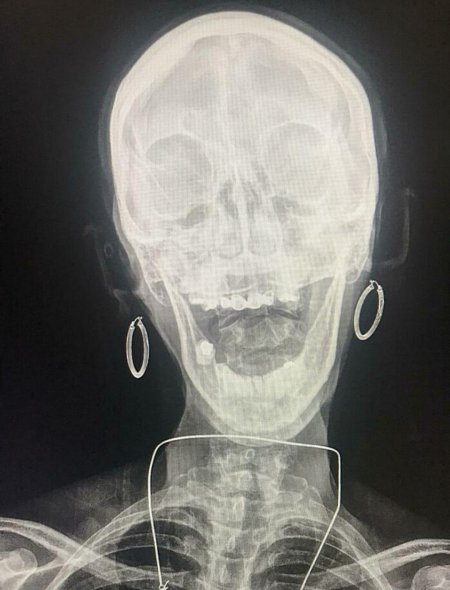

Рентгеновский эффект создает фантастические композиции в этих фотографиях девушки, чье тело становится прозрачным, демонстрируя скелет и внутренние органы. Она позирует в разных позах, ее силуэт светится загадочным свечением. Каждый кадр передает атмосферу научной фантастики и медицинского искусства. Ее кожа кажется полупрозрачной, позволяя увидеть кости и мышцы. Фотографии рассказывают о хрупкости человеческого тела и его внутренней красоте. Девушка то стоит в задумчивости, то делает грациозное движение. Эти иллюстрации вдохновляют на размышления о человеческой анатомии и уязвимости. Каждая картинка - это момент прозрения, когда внешнее уступает место внутреннему. Девушка воплощает образ современной Медузы, сочетающей красоту и загадочность.

Сквозь материю: тайны анатомии